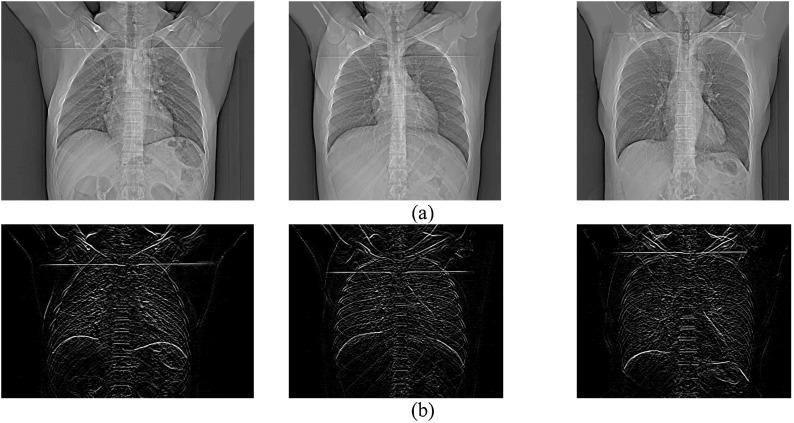

The coronavirus (COVID-19) is currently the most common contagious disease which is prevalent all over the world. The main challenge of this disease is the primary diagnosis to prevent secondary infections and its spread from one person to another. Therefore, it is essential to use an automatic diagnosis system along with clinical procedures for the rapid diagnosis of COVID-19 to prevent its spread. Artificial intelligence techniques using computed tomography (CT) images of the lungs and chest radiography have the potential to obtain high diagnostic performance for Covid-19 diagnosis. In this study, a fusion of convolutional neural network (CNN), support vector machine (SVM), and Sobel filter is proposed to detect COVID-19 using X-ray images. A new X-ray image dataset was collected and subjected to high pass filter using a Sobel filter to obtain the edges of the images. Then these images are fed to CNN deep learning model followed by SVM classifier with ten-fold cross validation strategy. This method is designed so that it can learn with not many data. Our results show that the proposed CNN-SVM with Sobel filter (CNN-SVM + Sobel) achieved the highest classification accuracy, sensitivity and specificity of 99.02%, 100% and 95.23%, respectively in automated detection of COVID-19. It showed that using Sobel filter can improve the performance of CNN. Unlike most of the other researches, this method does not use a pre-trained network. We have also validated our developed model using public databases and obtained the highest performance. Hence, our developed model is ready for clinical application.

冠状病毒(COVID-19)是目前全球最常见的传染病。这种疾病的主要挑战在于进行初步诊断以预防继发感染及其在人与人之间的传播。因此,使用自动诊断系统并结合临床程序对COVID-19进行快速诊断以防止其传播至关重要。利用肺部计算机断层扫描(CT)图像和胸部X光片的人工智能技术有潜力在COVID-19诊断中获得较高的诊断性能。在本研究中,提出了一种卷积神经网络(CNN)、支持向量机(SVM)和索贝尔滤波器的融合方法,用于使用X射线图像检测COVID-19。收集了一个新的X射线图像数据集,并使用索贝尔滤波器对其进行高通滤波以获取图像边缘。然后将这些图像输入到CNN深度学习模型,接着使用具有十折交叉验证策略的SVM分类器。该方法的设计使其能够在数据量不多的情况下进行学习。我们的结果表明,所提出的带有索贝尔滤波器的CNN-SVM(CNN-SVM + 索贝尔)在COVID-19自动检测中分别达到了最高的分类准确率、灵敏度和特异性,分别为99.02%、100%和95.23%。结果表明,使用索贝尔滤波器可以提高CNN的性能。与大多数其他研究不同,该方法不使用预训练网络。我们还使用公共数据库对我们开发的模型进行了验证,并获得了最高性能。因此,我们开发的模型已准备好用于临床应用。